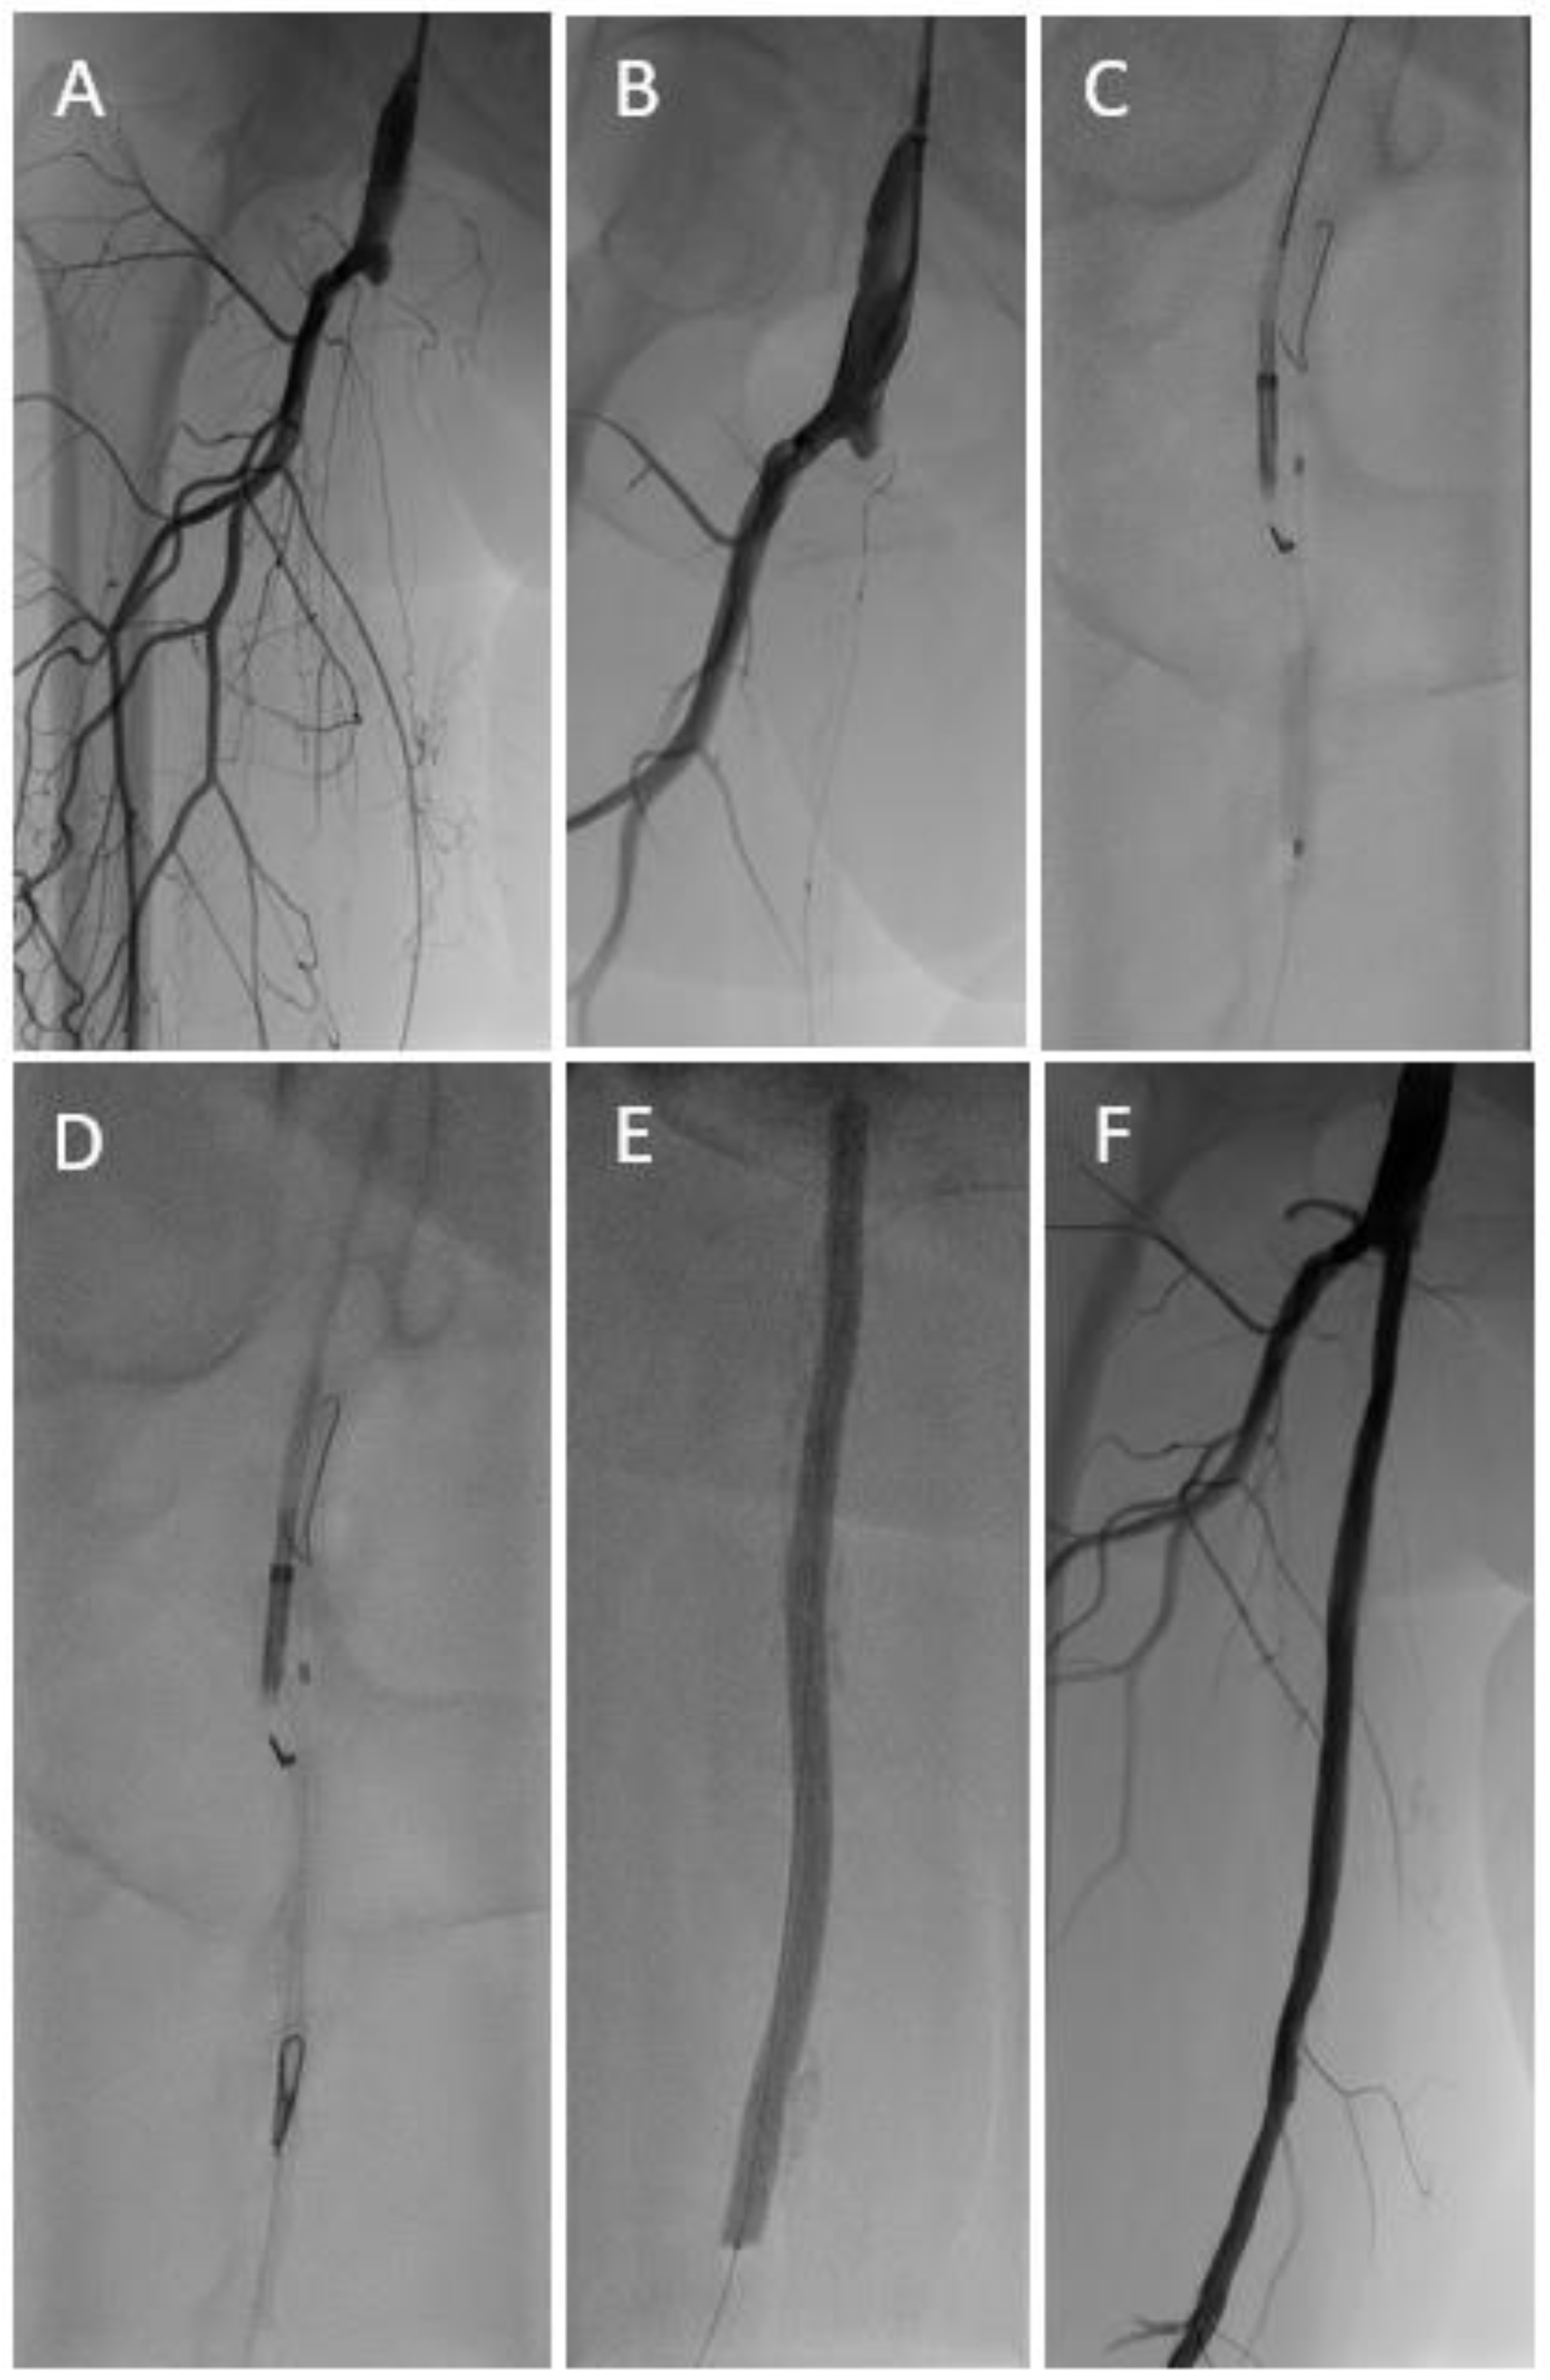

Figure 1.

Long occlusive lesion (A) with initially unsuccessful recanalization attempts via both the antegrade and retrograde (B) route. A target-balloon was inserted via the retrograde access and punctured with the re-entry needle of an Outback™ catheter (C,D). After predilatation with a standard balloon followed by drug coated balloon angioplasty (E), an acceptable result was achieved without the need for subsequent stent implantation (F).